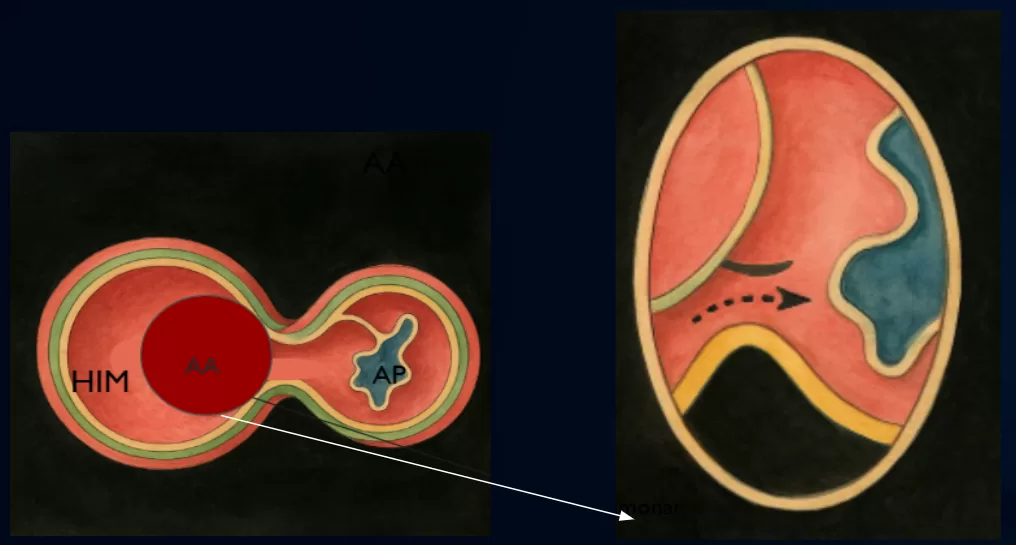

Tomografia Computadorizada de Tórax Sem Contraste

Janela mediastinal

AngioTomografia de Tórax